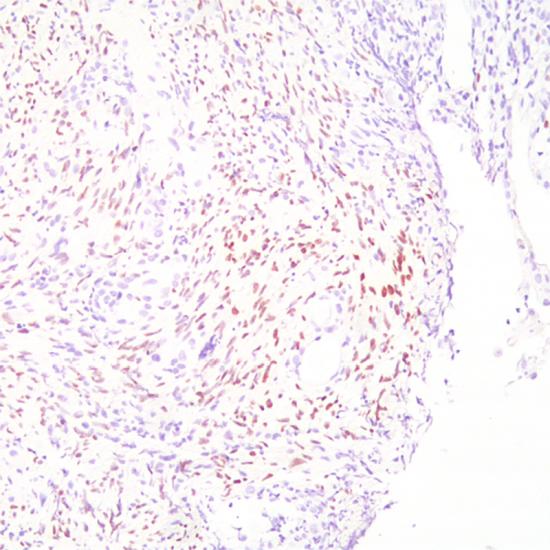

This antibody specifically identifies viral antigens in the nucleus of infected cells and produces a brown nuclear staining pattern in positive samples.

Clear brown nuclear staining